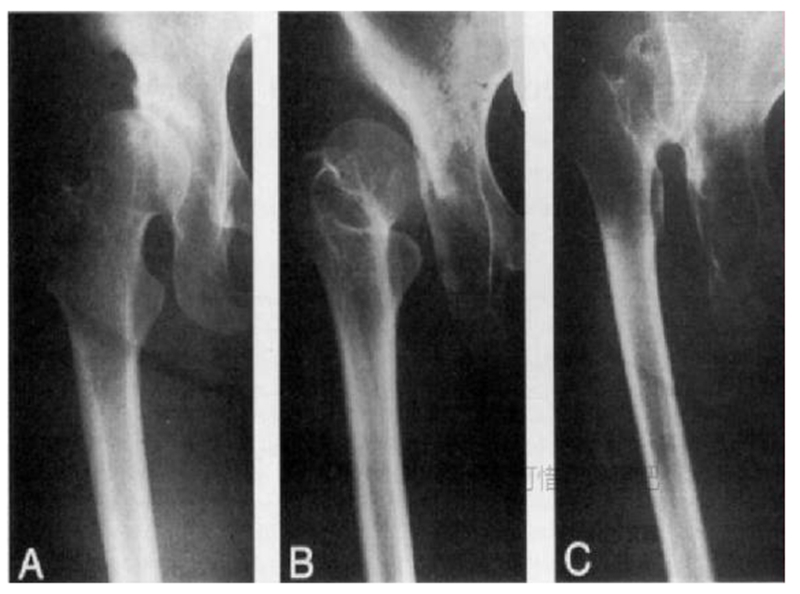

4、Kerboul分型

Kerboul于1987年提出根据矢状面上股骨头与髋臼的对应关系进行分型。

A型:髋关节前脱位,股骨头向前脱位,位于真臼的前方;

B型:髋关节中间脱位,股骨头与髂骨接触,与真臼处于同一冠状面上;

C型:髋关节后脱位,股骨头完全脱位后,位于真臼的后方或者上方。